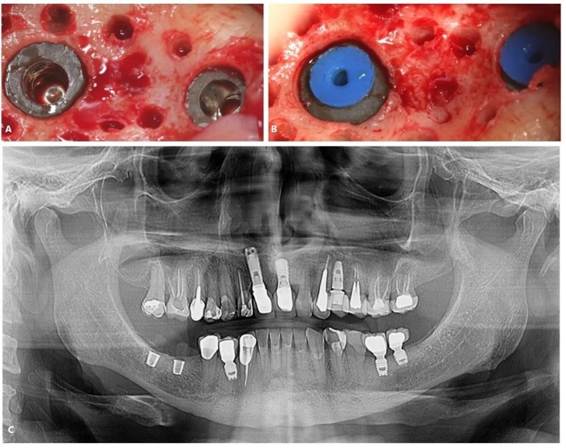

Paciente A. R. S, gênero feminino, 67 anos de idade, compareceu ao consultório particular, em 2020, com a queixa de mobilidade na região dos implantes inferiores. Na anamnese, paciente realizava acompanhamento médico devido ao quadro de diabetes mellitus, com uso de medicamentos específicos. Ao exame clínico, verificado mobilidade acentuada na regão do 36, 37, 46 e 47. Foram solicitados radiografia panorâmica (Figura 04. A) e tomografia computadorizada da área, evidenciando comprometimento periodontal avançado nas reabilitações com implantes dentários. O plano de tratamento proposto foi a remoção dos implantes e nova reabilitação da região atrófica.

Inicialmente, o procedimento cirúrgico consistiu pela remoção dos implantes dentários (Figura 04. B), realização de enxerto imediato (Bio-Oss, Geistlinch, Wolhusen – Suíça), através da técnica de reconstrução tipo tenda, e uso da membrana de colágeno (Bio-Gide, Geistlinch, Wolhusen – Suíça). O Quadro 1 apresenta as principais medidas para avaliação do posicionamento do implante. Após 6 meses, foram instalados dois implantes dentários extra curtos ARCSYS (FGM, Joinvile – SC, Brasil) 4,0 mm x 6,0 mm x 5,0 mm do lado direito e dois implantes na região esquerda 5,0 mm x 5,0 mm. As figuras 05 e 06 evidenciam aspecto radiográfico após a etapa inicial. As recomendações pós-operatórias e a prescrição medicamentosa foram realizadas, resultando em ausência de complicações após a intervenção. O acompanhamento foi feito durante 5 anos, com resultado satisfatório (Figura 7. A – E).

Figura 05. Exames de imagem da região inferior direita. A) Vista panorâmica. B) Reconstruções tridimensionais. C) Cortes transversais oblíquos.

Figura 06. Exames de imagem da região inferior esquerda. A) Vista panorâmica. B) Reconstruções tridimensionais. C) Cortes transversais oblíquos.

Figura 07. A – D) Aspecto final. E) Radiografia panorâmica final.